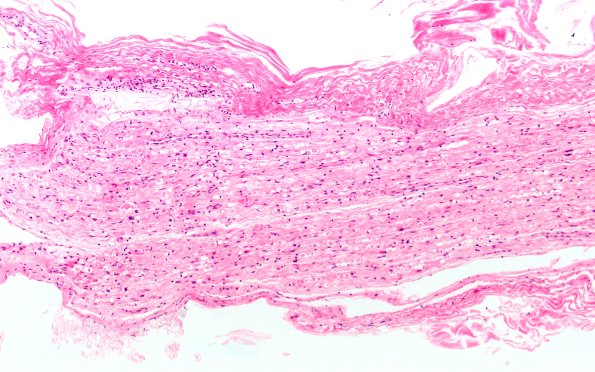

7B1 Ovoids (Case 7) H&E 10X

7B1-3 Numerous degenerating axons are seen in these longitudinal sections. (H&E)